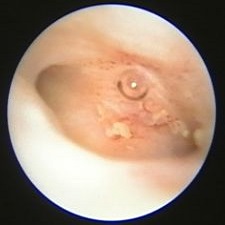

Nejčastější hysteroskopické nálezy

Odstranění drobných polypů a myomkůOdstranění